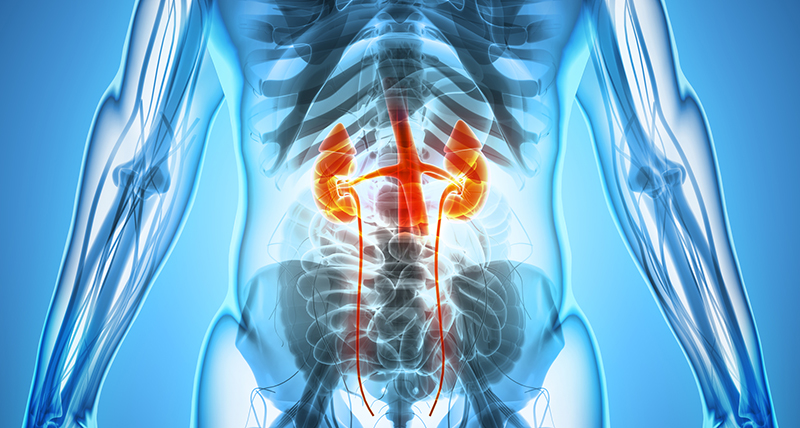

kidney cancer

Kidney cancer is cancer that begins in the kidneys. Your kidneys are two bean-shaped organs, each about the size of your fist. In adults, renal cell carcinoma is the most common type of kidney cancer.

Kidney cancer usually doesn't have signs or symptoms in its early stages. In time, signs and symptoms may develop, including: Blood in your urine, which may appear pink, red or cola colored, Pain in your back or side that doesn't go away, Loss of appetite, Unexplained weight loss, Tiredness and Fever.